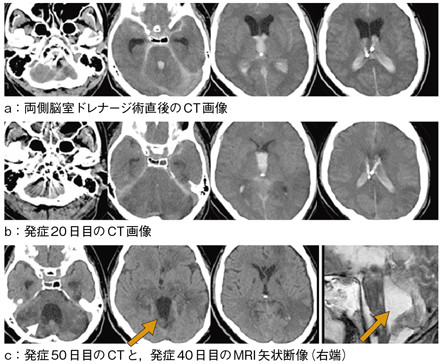

図2 CT経過とMRI

両側脳室ドレナージ術直後のCT(a)。発症2日目のCTでは血管攣縮のため小脳腫脹が著明であった(b)。

発症50日目のCT,発症40日目のMRI矢状断では第4脳室のみが拡大しIsolated Wth ventricleと診断した(c)。